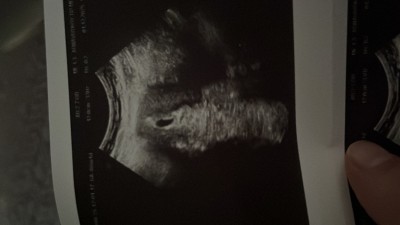

Bende bugün 5+1 im Dr çok kucukde olsa keseyi gordu bu şekilde

image